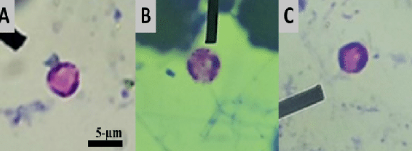

Plasmodium falciparum - gametocyt

100x

Plasmodium falciparum - pierścień

Plasmodium vivax - schizont

40x